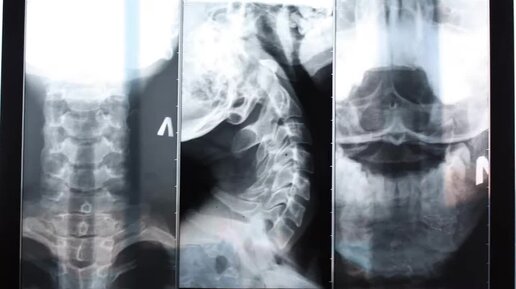

Почему болит затылок + признаки болезни